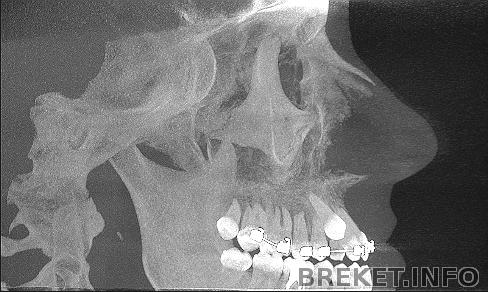

Вид сбоку

Вывод один - скорее бы операция

Striges, была, рассекали небный шов, будет остеотомия челюсти